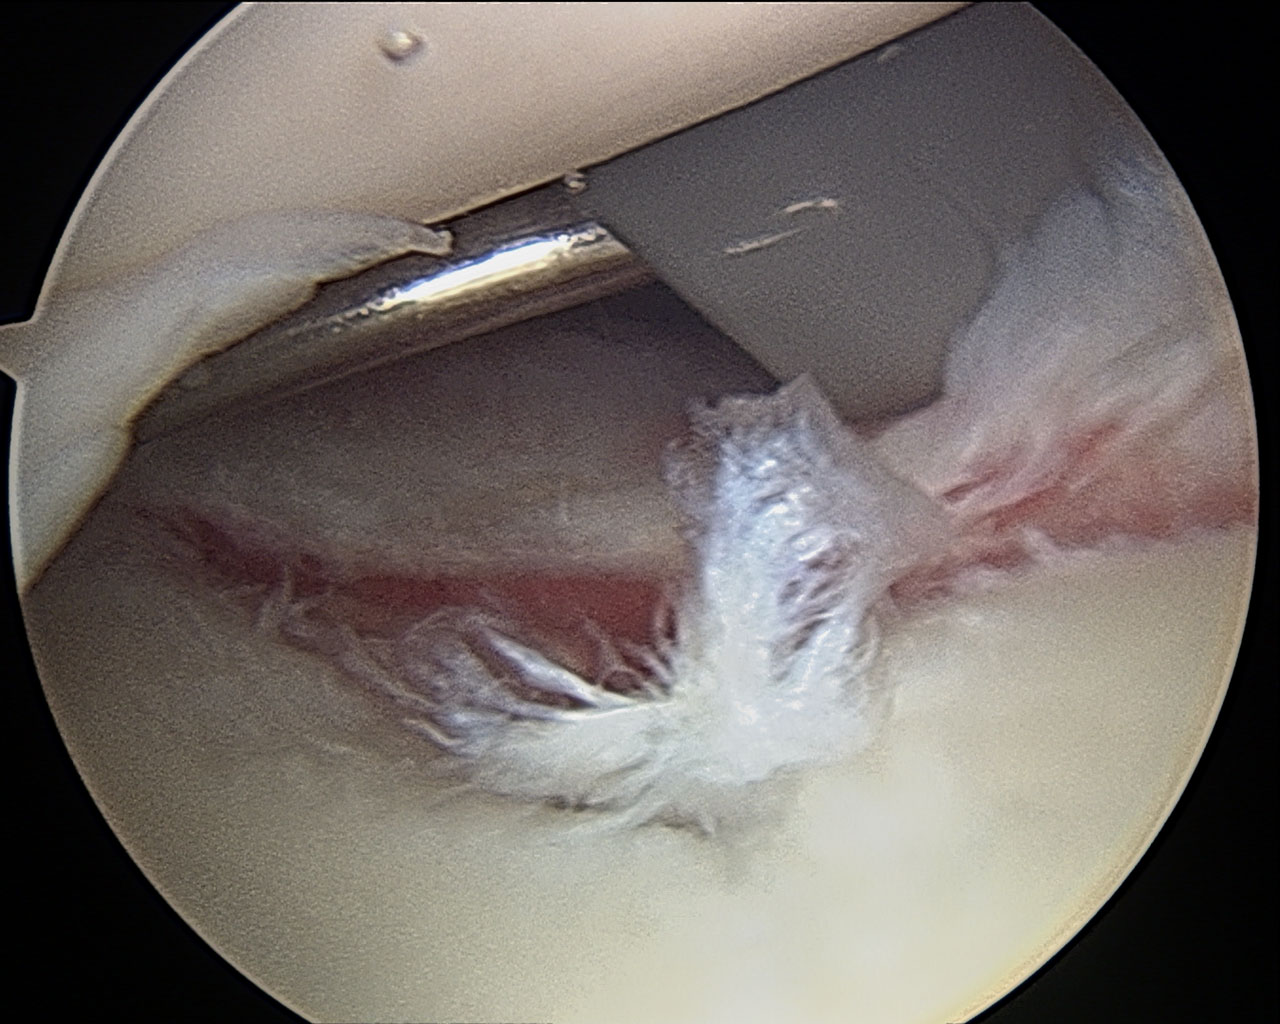

slap 2

anterior labrum flap & some glenoid fossa issues

2 for one and also because I was PRing on surgical procedures. #PReveryday  Turned out I had a lot of stuff going on in there: shaved the end of the “loose” acromiale, fixed a minor slap 2 tear, fixed a minor biceps tendon tear, sucked out some bursitis, cleaned up a large tear in the anterior labrum, and also cleaned up some fraying articular cartilage in the glenoid fossa. Yeah, lots of suck.  **second take home. stick to your training plan. especially the proper warm up. I did neither on both injuries and that isn’t gonna happen again.**